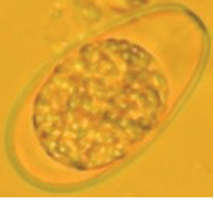

Cryptosporidium spp. (Cryptosporidiosis);

Oocysts (shed in feces);

~4-6 X 4.5-7 µm - No micropyle or micropylar cap, inner and outer walls are sealed closed by the suture.

Sporulated oocyst containing 1x0x4 architecture (0x sporocysts X 4x sporozoites total).